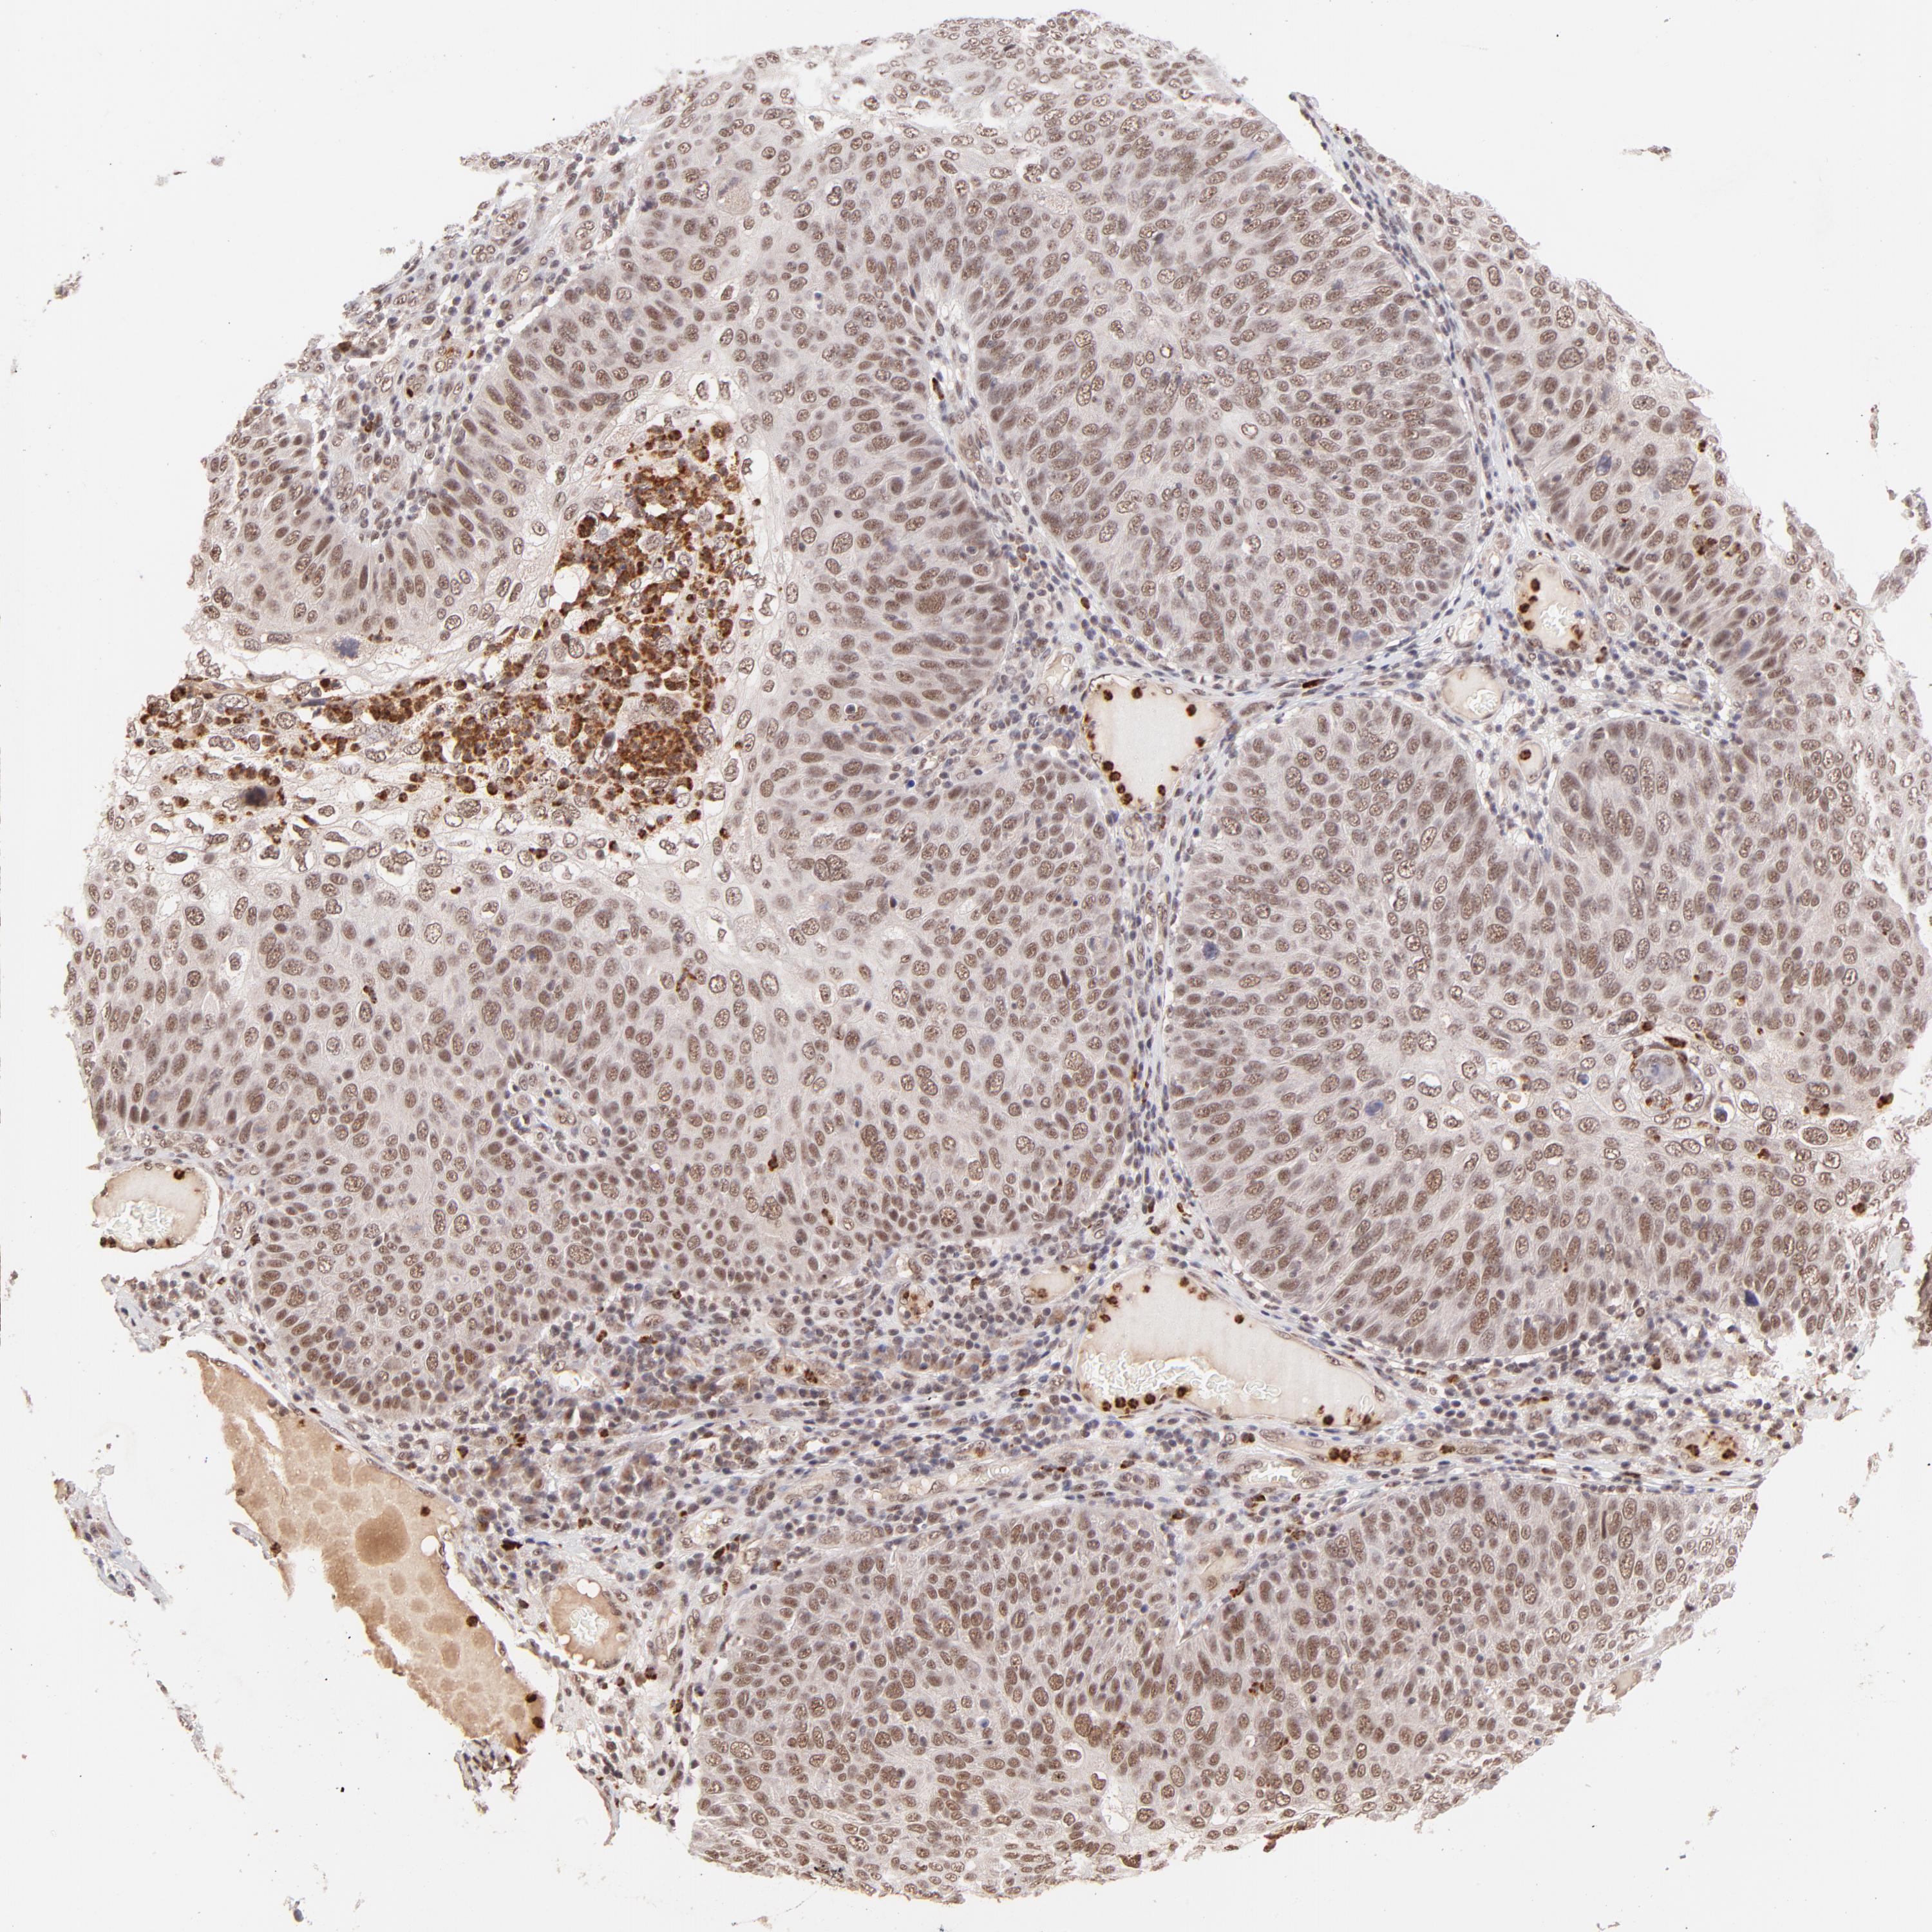

SKIN CANCER - Protein expressioni

A mouse-over function shows sample information and annotation data. Click on an image to view it in a full screen mode. Samples can be filtered based on level of antibody staining by selecting one or several of the following categories: high, medium, low and not detected. The assay and annotation is described here.

Antibody stainingi

Antibody staining in the annotated cell types in the current human tissue is reported as not detected, low, medium, or high, based on conventional immunohistochemistry profiling in selected tissues. This score is based on the combination of the staining intensity and fraction of stained cells.

Each image is clickable and will lead to virtual microscopy that enables deeper exploration of all samples and also displays staining intensity scores, fraction scores and subcellular localization as well as patient and tissue information for each sample.

Antibody HPA003184

Antibody HPA003185

Staining

High

Medium

Low

Not detected

Intensity

Strong

Moderate

Weak

Negative

Quantity

>75%

75%-25%

<25%

None

Location

Nuclear

Cytoplasmic/membranous

Cytoplasmic/membranous,nuclear

Squamous cell carcinoma, NOS

Basal cell carcinoma